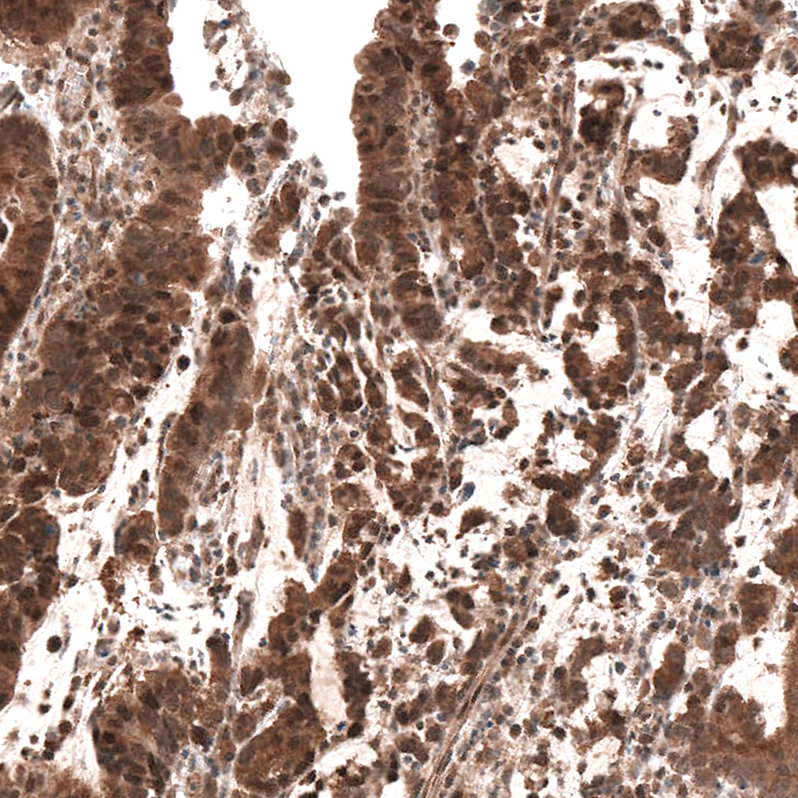

Immunohistochemical staining of human prostate shows moderate nuclear and cytoplasmic positivity in glandular cells.